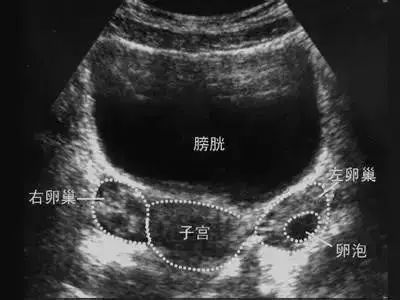

重庆送子鸟医院的医生指出:主要是由于阴道超声探头位置更接近子宫和卵巢,图像清晰,分辨率高,因此检查结果较为准确。所以,卵泡监测,阴道B超说了算!

阴道B超——为排卵监测护航初诊患者通过这项检查,可以帮助医生初步了解患者的子宫情况,内膜情况,卵巢储备功能,优势卵泡大小等,为患者的后续治疗提供依据。

其实监测排卵的方法有很多种,比如基础体温监测,试纸监测等,但是在所有监测排卵的方法中,阴道超声监测是目前最为准确的方法。它不仅可以测量出优势卵泡大小,内膜厚度等,并且对部分因宫外孕单侧输卵管切除后的患者来说,还可以通过B超观察本周期是在哪一侧卵巢排卵,从而避免一些不必要的花费。

一般在月经周期的第10天左右开始监测,卵泡平均以每日2mm的速度增长,连续监测可见卵泡不断长大,达到18mm时就成为成熟卵泡了,当最大的卵泡消失时,提示发生排卵。